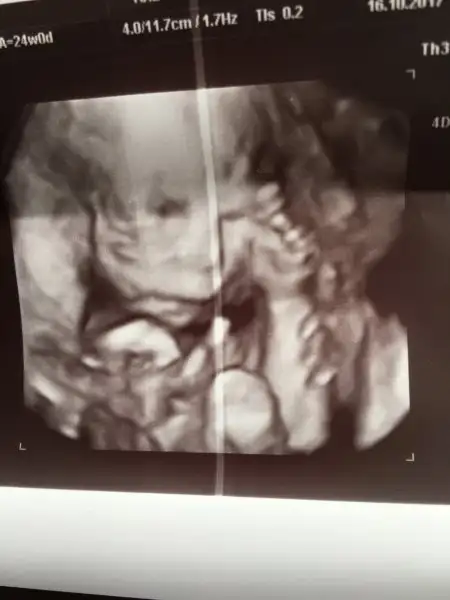

Pitircik yerim seni...Eki Görüntüle 2055849 Eki Görüntüle 2055850 Günaydın canlar bakın kızıma

28,5 cm 560 gr olmuş kızım :) Plasenta azcık yana kaymış biraz daha kayarsa kurtaracak ama şuan hala bebeği alacağımız yerde olduğu için kanama riski var dinlenmene devam et tamam mı dedi